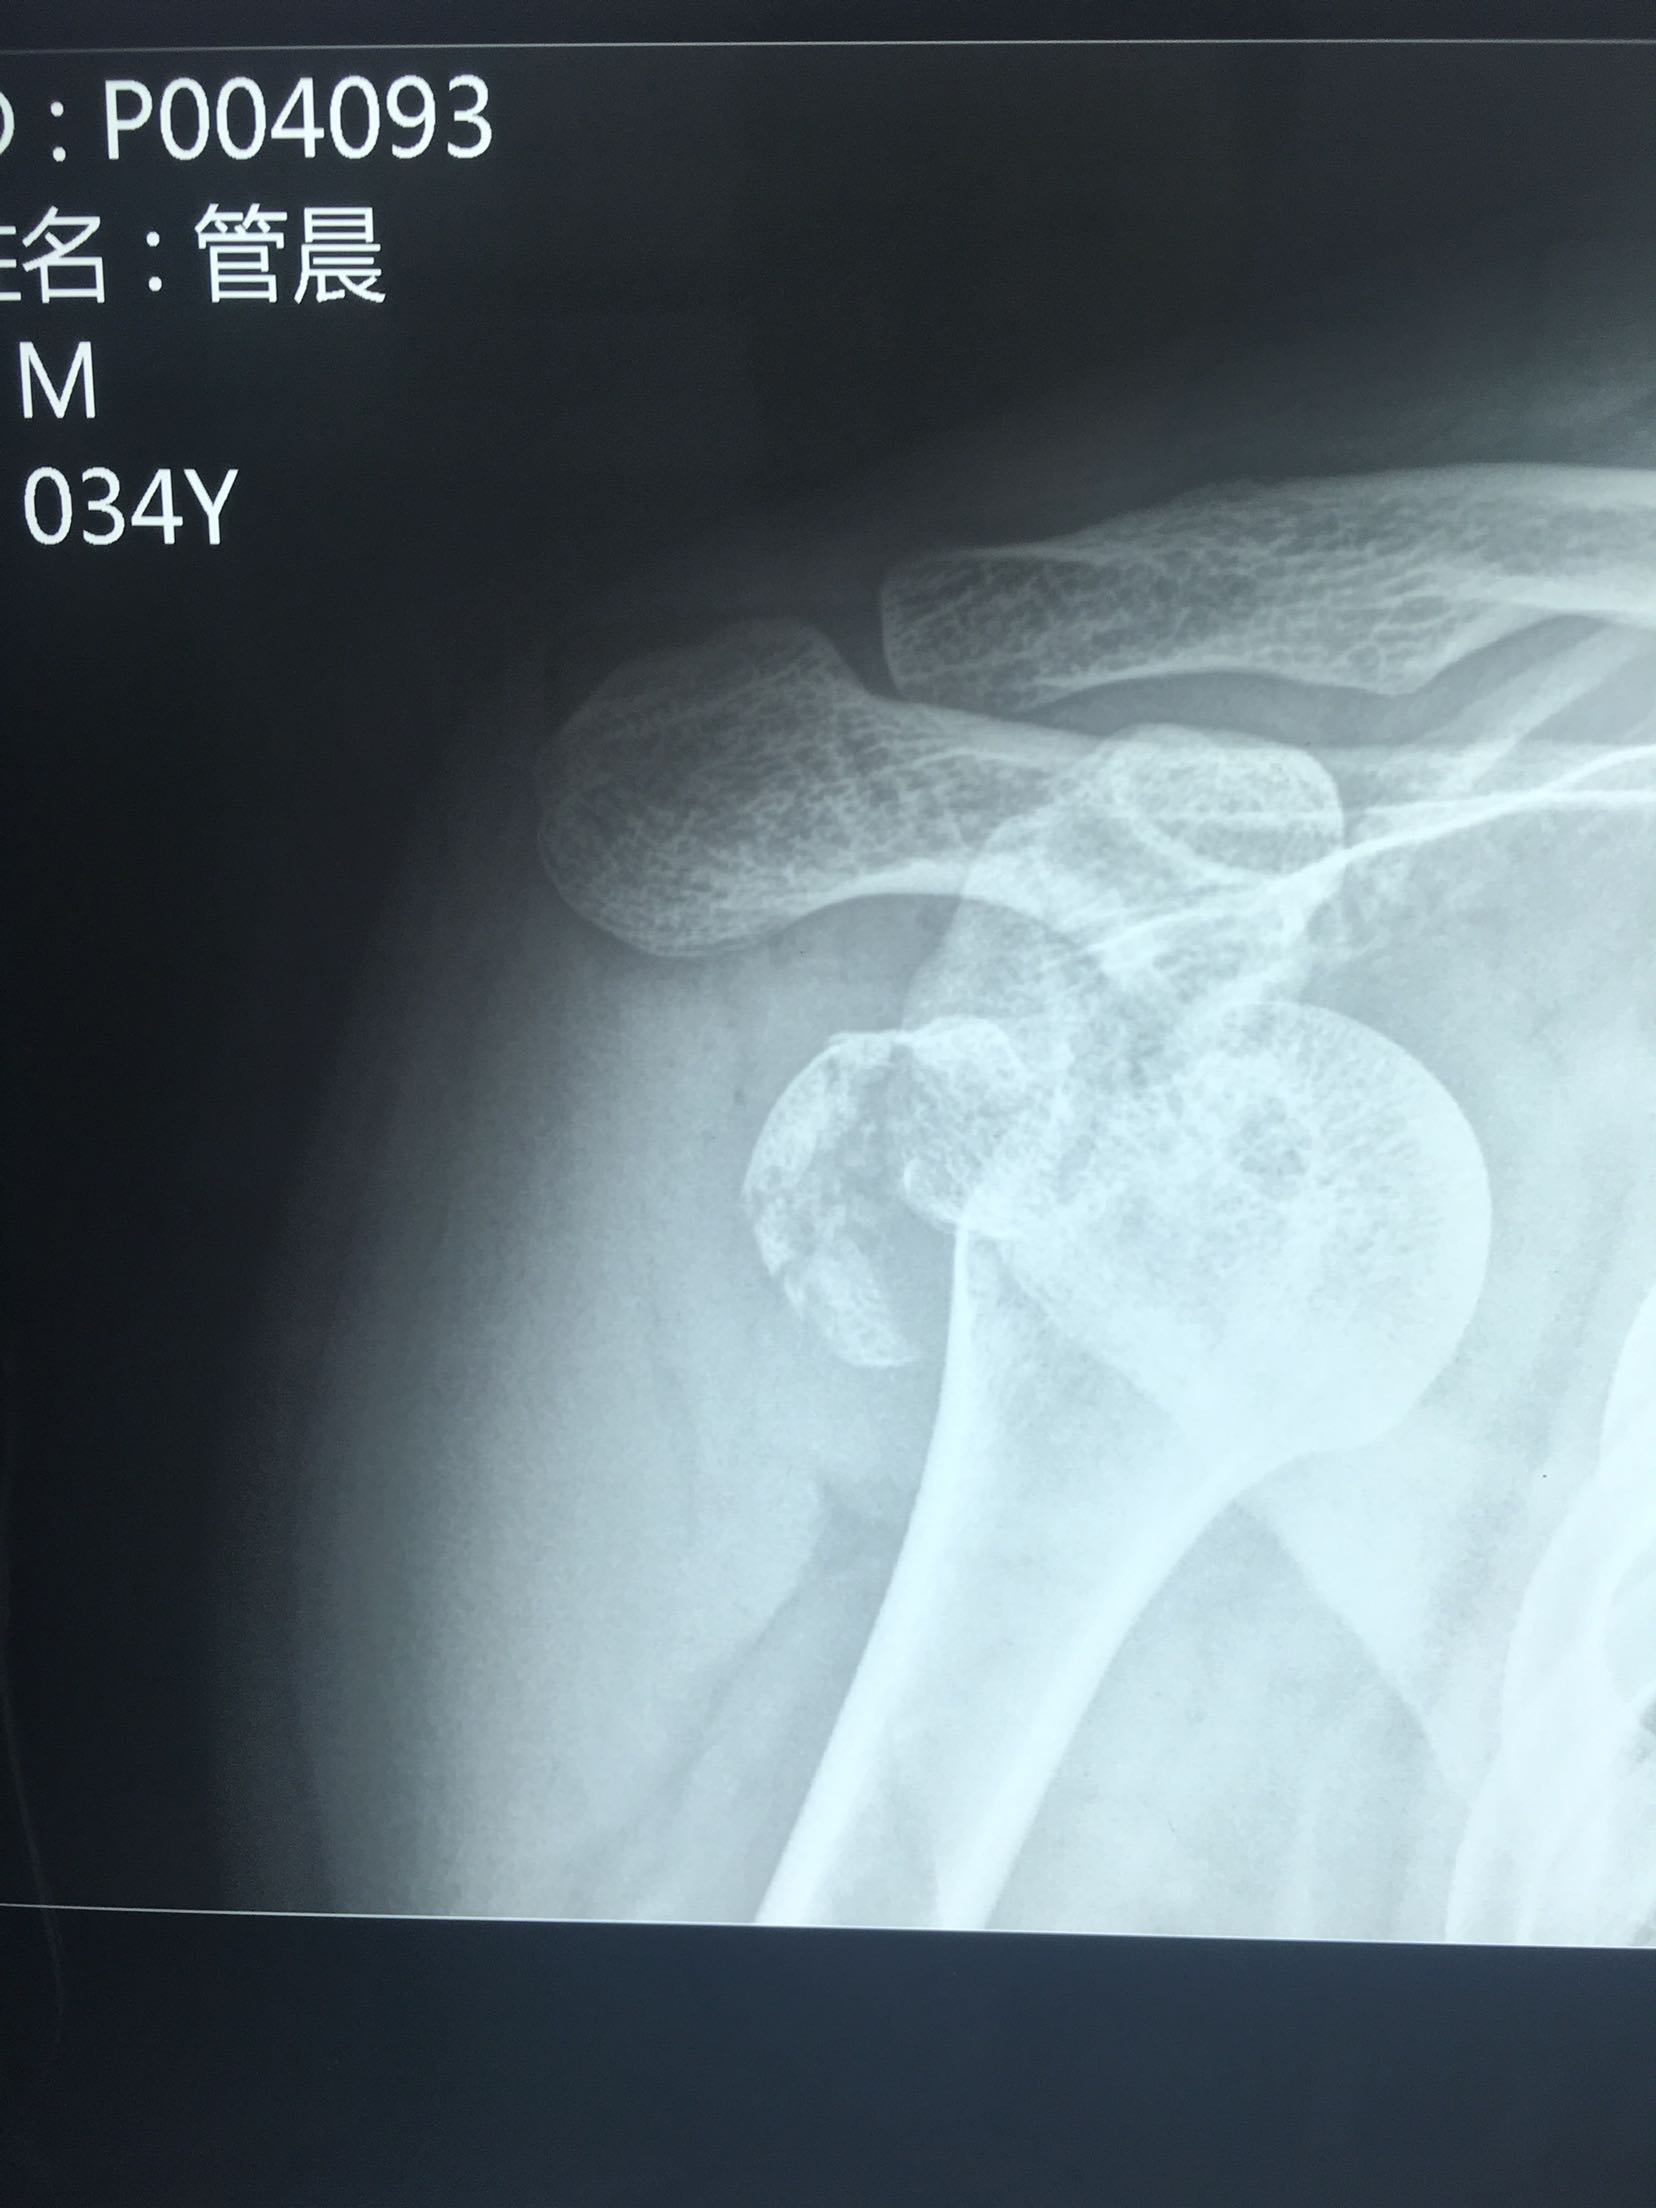

肩关节脱位并大结节骨折

肩关节脱位并骨折

右肩关节脱位并肱大结节撕脱性骨折